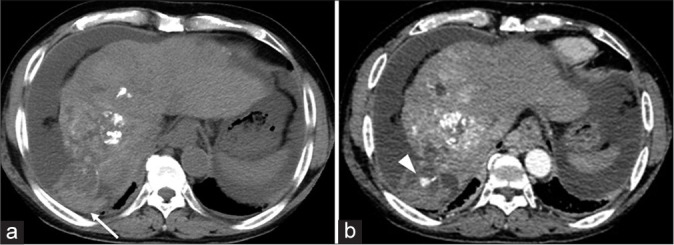

We present a case involving a 60-year-old male with multifocal hepatocellular carcinoma (HCC), emphasizing the critical need for vigilant post-procedural monitoring following the interruption of drug-eluting beads transarterial chemoembolization (DEB-TACE) due to an allergic reaction. The patient, who had a history of various treatments for HCC, underwent DEB-TACE. During the procedure, he experienced an anaphylactic shock, presumably due to an allergy to the treatment components (iodinated contrast agent), resulting in the procedure's discontinuation. Initially stable, the patient was later found to have intra-abdominal bleeding, a complication associated with the vascular lake phenomenon (VLP), detected on post-procedural imaging. Re-embolization using gelatin particles was performed to address the VLP. It remains unclear whether the shock experienced during the DEB-TACE procedure was due to the allergic reaction or the rupture of the VLP. This case underscores the complexities in managing DEB-TACE, the necessity of careful monitoring for VLP, and the challenges in diagnosing and managing allergic reactions during such procedures. In conclusion, it is crucial to consider that VLP can occur at any time during or after DEB-TACE. Assessing the presence of VLP using digital subtraction angiography before the termination of the procedure is essential. However, when an allergy to the iodinated contrast agent is suspected, as in this case, careful follow-up with abdominal ultrasound and computed tomography might be necessary to assess the presence of intra-abdominal hemorrhage associated with VLP.

我们介绍了一例 60 岁男性多灶性肝细胞癌(HCC)患者的病例,强调了因过敏反应而中断药物洗脱珠经动脉化疗栓塞术(DEB-TACE)后进行术后监测的重要性。患者曾接受过多种 HCC 治疗,接受了 DEB-TACE。在手术过程中,他出现了过敏性休克,可能是由于对治疗成分(碘造影剂)过敏,导致手术中止。患者最初病情稳定,但后来发现腹腔内出血,这是一种与血管湖现象(VLP)有关的并发症,在手术后的成像中被发现。为解决 VLP 问题,使用明胶颗粒进行了再次栓塞。目前还不清楚 DEB-TACE 过程中出现的休克是由于过敏反应还是 VLP 破裂所致。该病例突出说明了 DEB-TACE 管理的复杂性、仔细监测 VLP 的必要性以及在此类手术中诊断和管理过敏反应的挑战性。总之,必须考虑到在 DEB-TACE 期间或之后的任何时候都可能出现 VLP。在手术终止前使用数字减影血管造影术评估是否存在 VLP 至关重要。不过,如果怀疑患者对碘化造影剂过敏,就像本病例一样,可能需要通过腹部超声波和计算机断层扫描进行仔细随访,以评估是否存在与 VLP 相关的腹腔内出血。